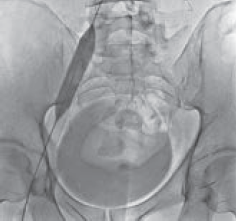

Рис. 3. Антеградная илеокаваграфия у пациента М., 39 лет, с выраженной тазовой симптоматикой (боли, эректильная дисфункция, хронический калькулезный простатит) вследствие синдрома Мея – Тюрнера: а — антеградная катетеризация левой общей подвздошной вены; б — при введении рентгеноконтрастного вещества отмечается его ретроградный заброс и контрастирование венозных сплетений малого таза (коллатеральное кровообращение); в — после контрастирования венозных сплетений малого таза рентгеноконтрастное вещество перераспределяется в правую общую подвздошную вену. Диаметр правой общей подвздошной вены в 1,4 раза меньше диаметра левой общей подвздошной вены

Рис. 4. Антеградная илеокаваграфия пациента М., 39 лет, от 28.03.2017. Отмечается компрессия левой общей и левой наружной подвздошных вен. Оперативный доступ из левой подколенной вены. Положение пациента на животе